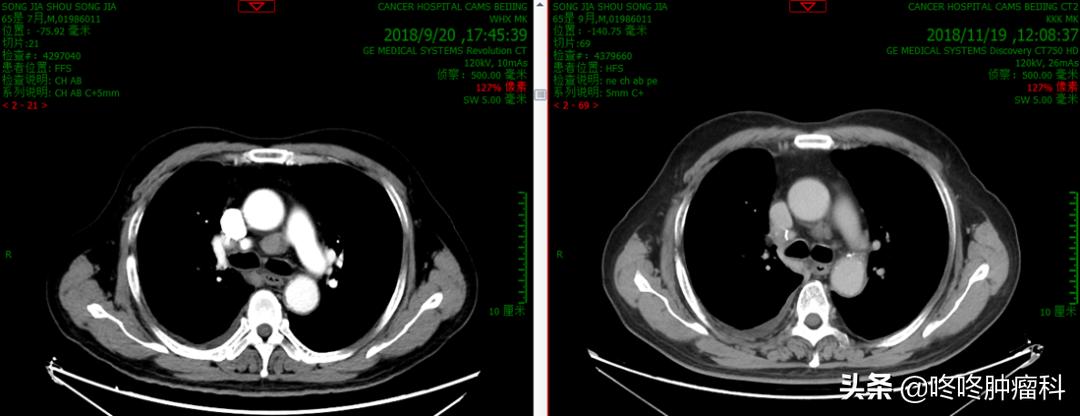

最佳疗效达到部分缓解PR,两个周期治疗以后,锁骨上纵膈淋巴结明显缩小,肺内小结节基本无变化。

左:治疗前;右:治疗后2周